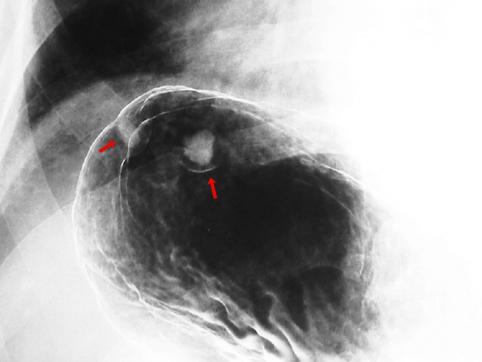

질환(병리주체)의 분류 종양양 병변/벽석탄화 병변

부위(장기별) 위(부위)/궁륭

검사방법 X-P

종양의 최대경(밀리미터) 1~9